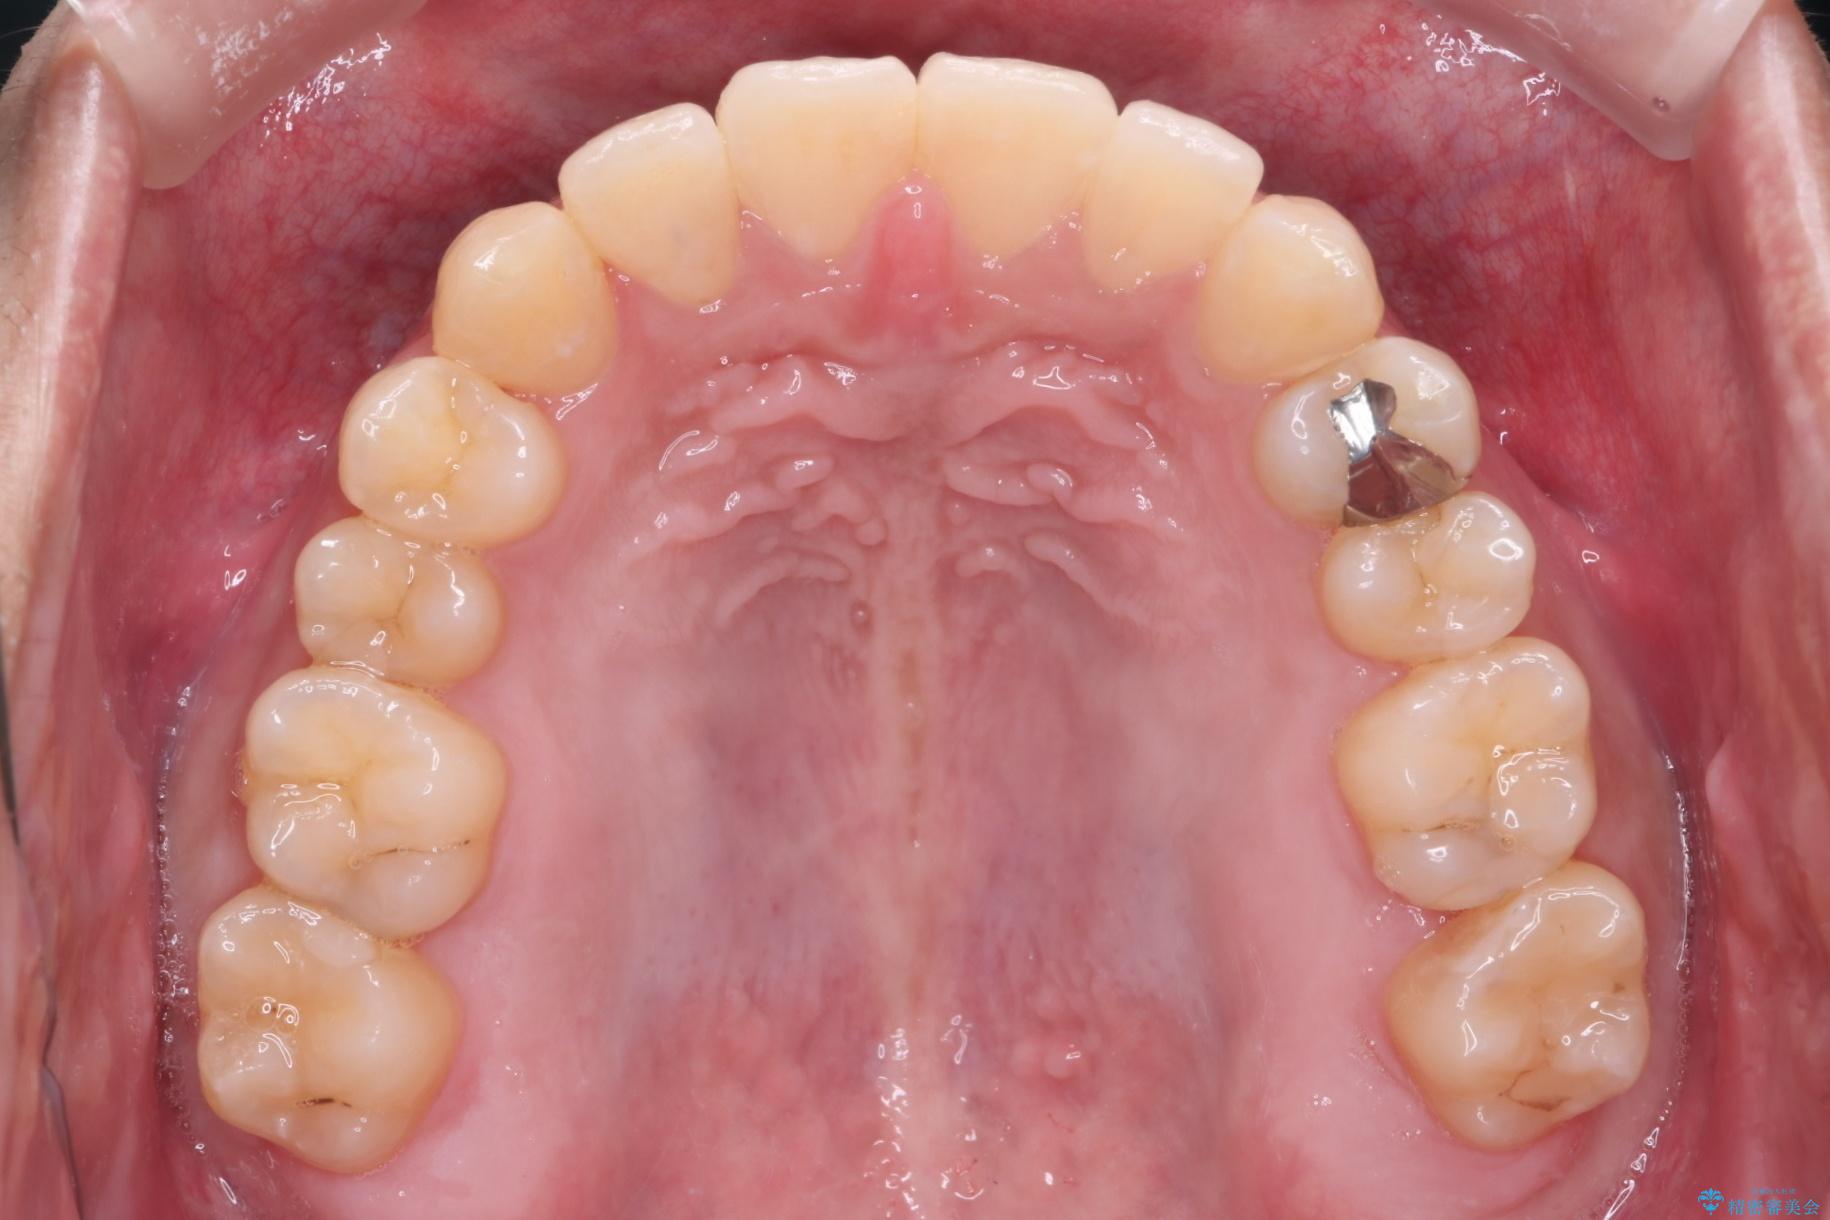

目立ちにくいクリア装置で八重歯とがたつきの改善

非抜歯での治療だったため、1年半以内という短い期間で矯正を終了することができました。主訴であった八重歯とがたつきが改善され、大変ご満足いただきました。

精密検査の結果、抜歯の必要はないと判断しました。臼歯を遠心移動させ、歯列をワイヤーで整えることでスペースを確保し、IPR(歯と歯の間を削る処置)を加えて歯並びを綺麗にする治療計画を立てました。